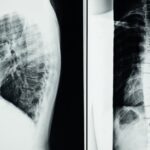

La décompression spinale est une manipulations non chirurgicale des vertèbres, destinée à créer un espace entre celles-ci. Cette technique permet de diminuer la pression exercée sur les disques intervertébraux et de faciliter le soulagement des douleurs. Cette méthode est souvent utilisée pour traiter des affections telles que les hernies discales ou les douleurs lombaires chroniques.

Le processus de décompression spinale repose sur l’application d’une force de traction douce sur la colonne vertébrale. Cette traction a pour effet d’étirer légèrement les espaces entre les vertèbres, ce qui permet de relâcher la pression sur les nerfs. Grâce à cette technique, les cellules et les tissus peuvent régénérer plus efficacement les zones endommagées, ce qui conduit à une guérison durable.

La décompression spinale est une méthode non-invasive qui vise à soulager la pression exercée sur les disques intervertébraux, ainsi que sur les racines nerveuses et les structures environnantes. Elle repose sur l’application d’une traction douce sur la colonne vertébrale, créant un espace entre les vertèbres. Ceci permet de réduire la compression et d’optimiser le flux sanguin, favorisant ainsi la guérison des tissus abîmés. La décompression est particulièrement utile pour traiter des problèmes tels que les hernies discales, la douleur lombaire chronique, et d’autres conditions entraînant des douleurs aiguës ou persistantes.